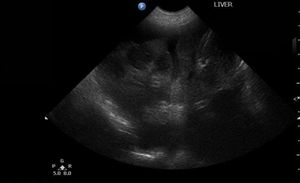

Dr. Garret Pachtinger explains how this technology is becoming more accessible in every-day practice, in terms of both cost and learning curve.

Since ultrasonography is becoming more accessible to all veterinary practitioners, learn all about this ultrasonographic examination protocol for trauma and start saving lives.